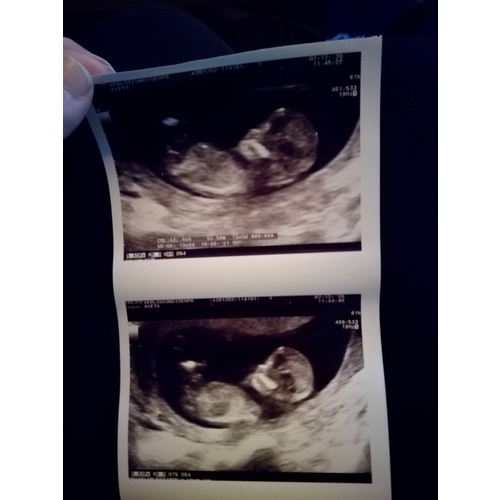

Hier een foto trouwens

Ze maakte er al mooie koprollen bij! Nu een heerlijk beweeglijk meisje 🥰